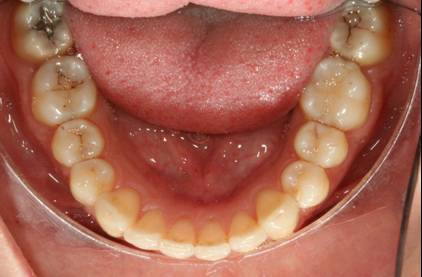

Trattamento soggetto adulto parodontopatico - Trattamento con mascherine invisibili

Il trattamento ha previsto l'utilizzo di 20 mascherine per l'arcata superiore e 13 per l'arcata inferiore.